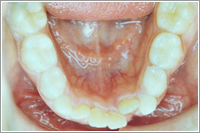

下の前歯がでこぼこに並んでいます。